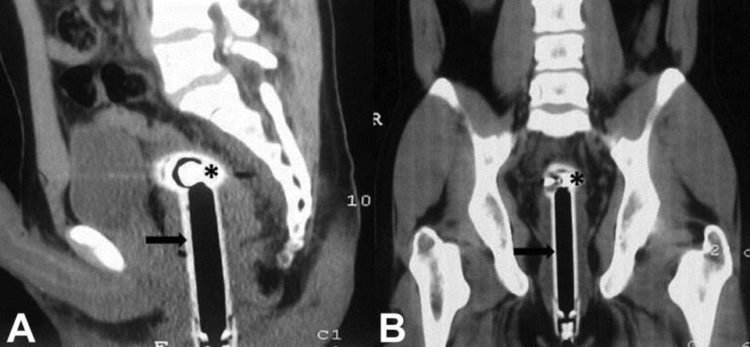

Radiografia imbarazzante al pronto soccorso: «Sono scivolato ...